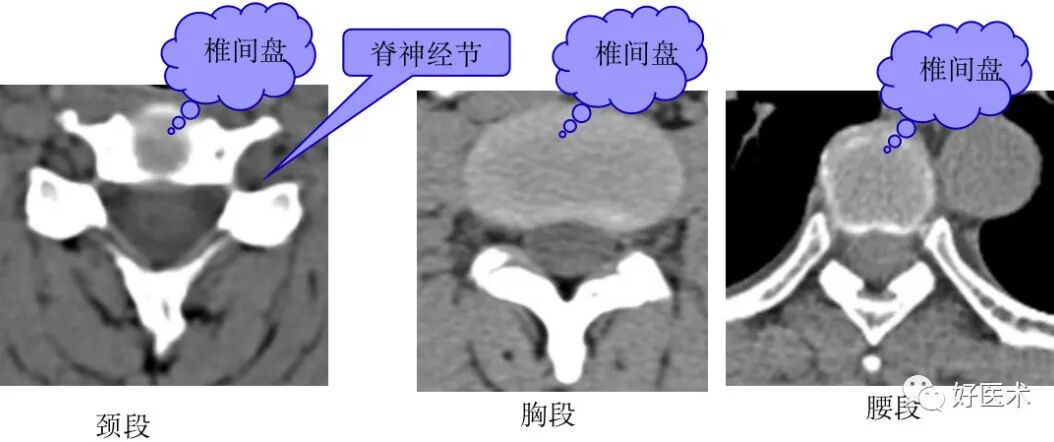

1. 经椎弓根的横断层面:

断面经过的部位:椎弓根

主要特征:椎管为完整性骨环,由椎体、椎弓根和椎弓板构成

2. 经椎体下部的横断层面:

断面经过的部位:椎弓根下方的椎体。

主要特征:椎管为不完整的骨性环,其断开处为椎间孔上部。

经过不同部位的椎间孔上部的结构不同,颈段主要为椎间静脉,胸、腰段主要为脊神经根。

3. 经椎间盘的横断层面:

断面经过的部位:椎间盘

主要特征:椎管呈不完整的骨性环,其断开处为椎间孔下部,不同部位椎间孔下部经过的结构不同,颈段主要为脊神经根,胸腰段主要为椎间静脉。